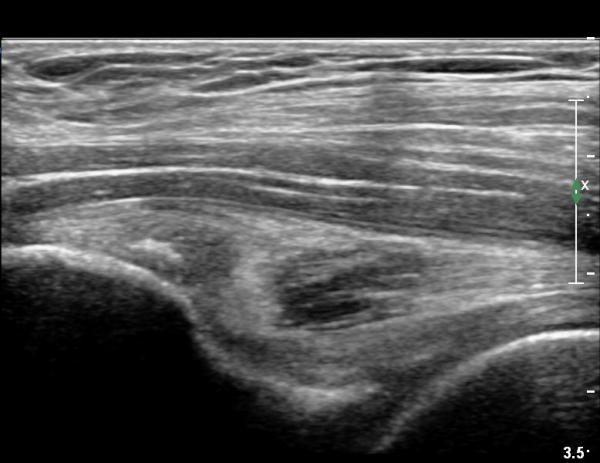

[¾ûµ¢ÀÌ] ÀüÇÏÀå°ñ±Ø °ß¿­°ñÀý(avulsion fracture of anterior inferior iliac spine)

Ç㸮¿Í ¾ûµ¢ÀÌ ÅëÁõ°ú ¿ìÃø ´Ù¸® ¶¯±è (±ÝÀÏ)

±ÝÀÏ ³Ñ¾îÁø ÈÄ ¸ñ, Ç㸮, ´Ù¸®ÀÇ ÅëÁõÀÌ ¹ß»ý. °ÉÀ» ¶§ ´Ù¸®°¡ ¾Èµé¸°´Ù.

´Éµ¿Àû SLR ¾ÈµÊ. ÀúÇ׿¡ ´ëÇÑ °í°üÀý ±¼°î°ú ¹«¸­ ½ÅÀü ½Ã ÅëÁõ°ú ±Ù¾àÁõÀ» º¸ÀÓ.